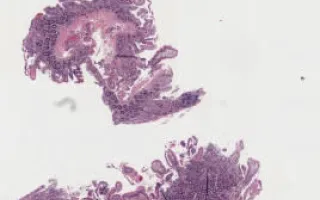

Giardia species (most commonly G. lamblia) are protozoal microorganisms found in water and can cause watery and foul smelling diarrhea. In addition to diarrhea, abdominal pain with abdominal fullness with flatulence is common. Giardia produces a physical barrier to absorption of luminal contents by coating the small bowel lumen. The histologic findings are of mild to moderate villous blunting and increased inflammatory cells in the lamina propria. Sometimes, the binucleate trophozoite forms of the organisms can be seen near the luminal surface.